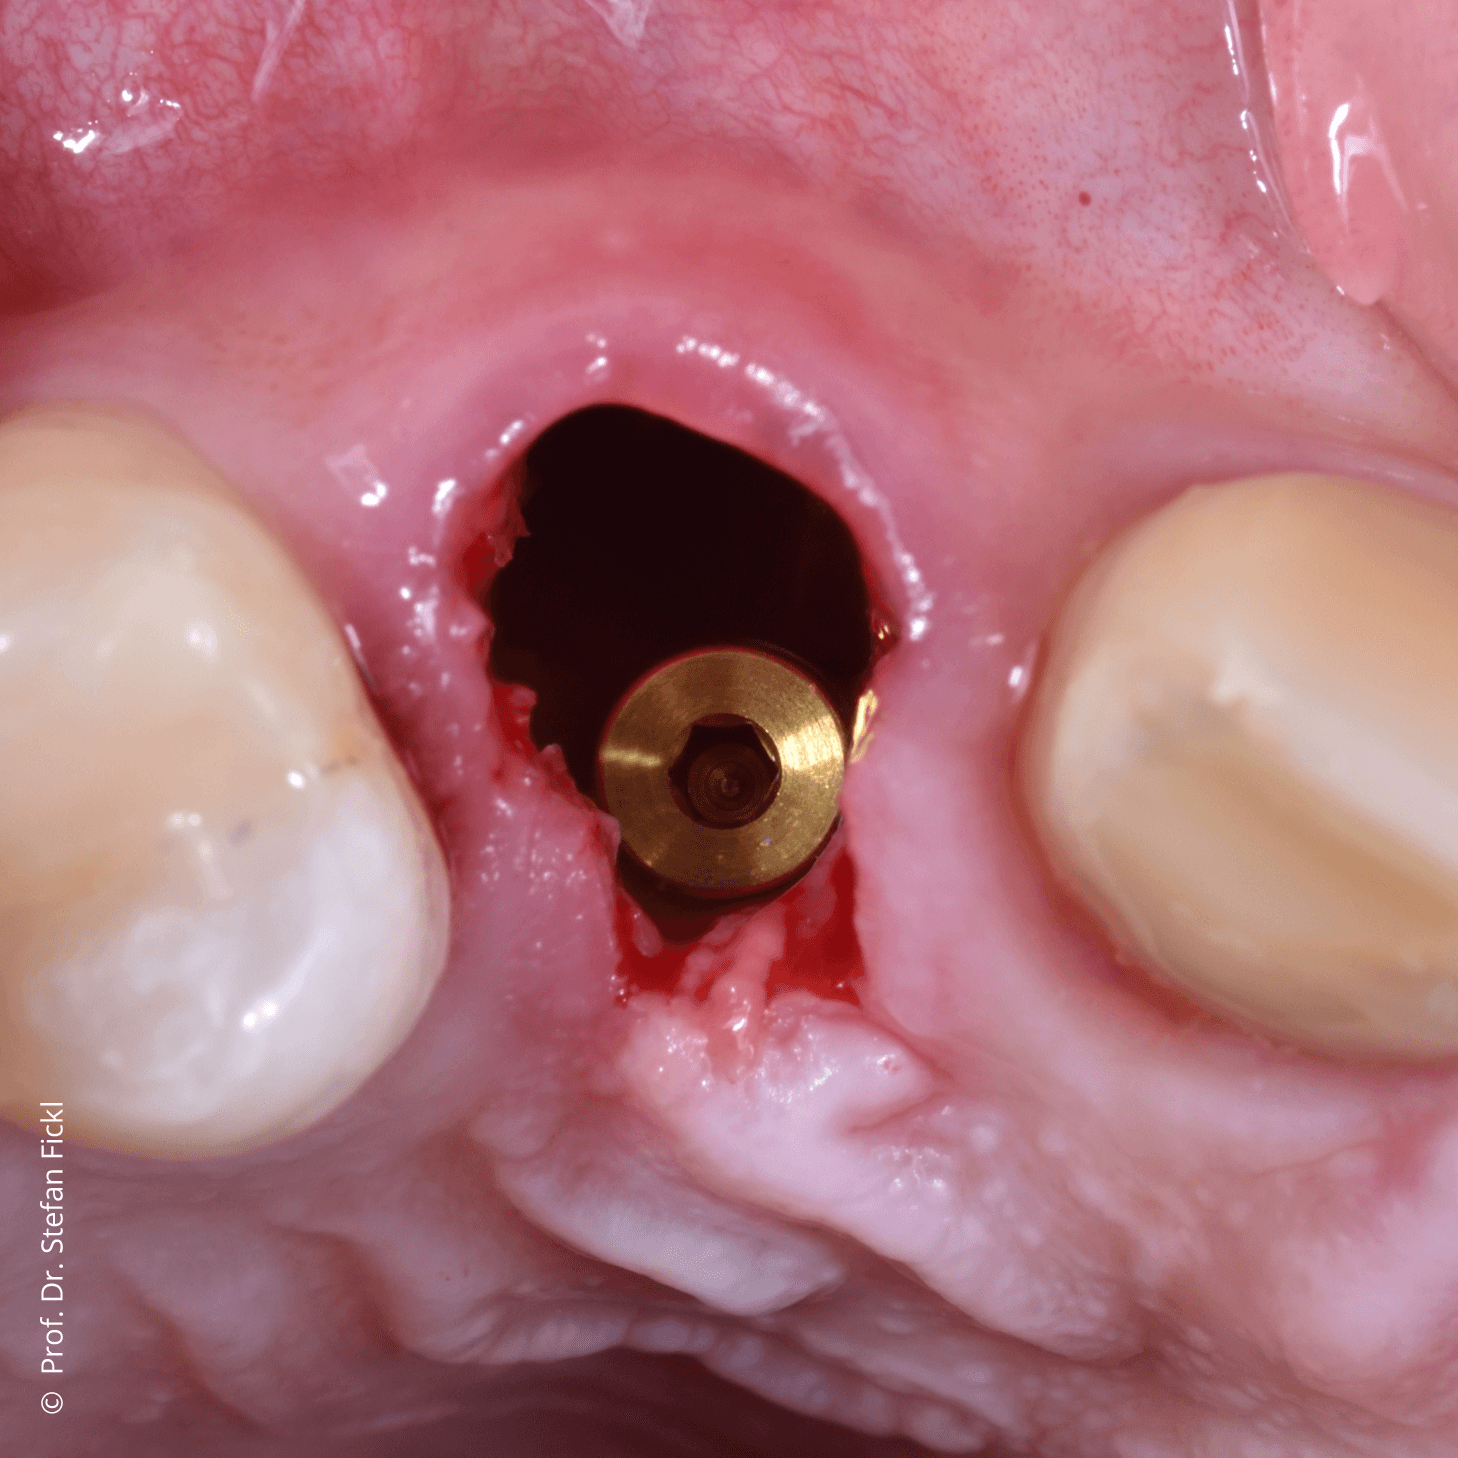

Im Gebiet der Hart- und Weichgewebechirurgie sowie der oralen Implantologie stellen erfahrene Referenten vor, welche Materialien sich für welchen Einsatz und welche Indikationen eignen. In Vortragsveranstaltungen, aber auch bei Live-OP-Kursen und Hands-on-Übungen lernen Sie den Einsatz der Biomaterialien besser kennen und können das Erlernte bei praktischen Übungen gleich direkt anwenden.